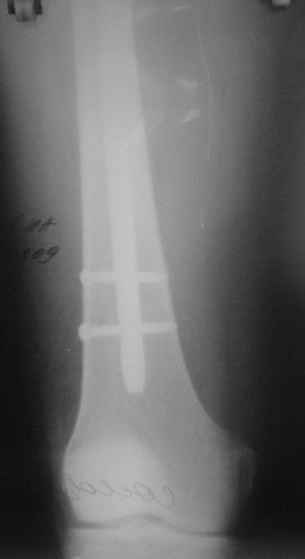

Сегодня прооперировали без открывания. Хотел-бы услышать комментарии по поводу послеоперационной нагрузки.

Учитывая изначальные снимки и то. что сделали , не открывая - весьма достойно. Доктор Коган прав - перелом немного перерастянут ( что хорошо видно по фибуле), а перерастянутые переломы большеберцовой срастаются очень плохо. Поэтому я бы обязательно дал раннюю динамизацию - на 6 неделях ( когда можно не опасаться малротации) разблокировал бы проксимальный фрагмент полностью и начал бы нагружать ногу. Будьте готовы к остеотомии ( или остеоэктомии участка) малоберцовой чеерз несколько месяцев- уж слишком хорошо стоит - очень вероятно, что срастется рано и будет держать большеберцовую перерастянутой

вдогонку - до разблокирования нагружать противопоказано - все, чего добьетесь - погнете шурупы. причем, если погнете дистальные ( как обычно бывает) - гвоздь провалится в сустав. Нагружайте птолько после проксимальной динамизации, когда будете уверены, что гвоздь поднагрузкой будет смещаться вверх, а не вниз

По представленым снимкам, "контакт" между отломками не очень =(. А боковой проекции нет?

Уважаемый Юрий Алексеевич, сложный перелом, смелое решение, хорошее исполнение и, надо надеяться, хороший будет результат. Но, что бы он (результат) был достойным, надо подготовиться и к худшему. В чём, с моей точки зрения, главная проблема, которую придётся решать. Да, вне всякого сомнения, система нуждается в ранней динамизации в совокупности с ранней же нагрузкой. В данном случае, мне кажется, можно было бы решиться и на первичную динамизацию, то есть проксимально блокировать гвоздь только через овальное отверстие, отказавшись от введения винта через круглое отверстие. В этом случае и нагрузку можно было бы начать раньше, чем через 6 недель, не опасаясь перелома дистальных винтов. Однако, имеющееся лёгкое вальгусное смещение может прогрессировать в случае полной нагрузки, которую, как справедливо отмечено форумом, требует имеющееся стояние отломков. И предотвратить дальнейшее вальгирование может достаточная наружная опора, которая возможна при хорошем стоянии поперечного перелома малоберцовой кости даже без его внутренней фиксации, как раз как в представленном случае. А, в то же самое время, раннее сращение малоберцовой кости может препятствовать консолидации большеберцовой кости. То есть, своеобразный замкнутый круг может получиться. И так, главная проблема, с которой мы можем здесь столкнуться зависит не от диастаза между основными фрагментами, и не от вальгуса, и не от хорошей репозиции поперечного перелома малоберцовой кости - а от совокупности всех трёх факторов.

Поэтому, мне кажется, пациент будет требовать постоянного внимания на этапе реабилитации. И, помимо темпа консолидации, контроля положения дистального конца гвоздя из за опасения пенетрации сустава, не меньшего внимания будет заслуживать и угловое стояние отломков. Мне кажется, что в случае отсутствия формирования периостальной мозоли в допустимые сроки вряд ли будет целесообразным выполнение остеотомии малоберцовой кости. Это, равно как и хотя бы незначительное усугубление вальгуса может послужить основанием для переустановки гвоздя. Но - это худший вариант, который, я надеюсь, не случится. Но о котором нужно помнить.

АВ> Однако, имеющееся лёгкое вальгусное смещение

Что-то не то тут с вальгусом. По положению гвоздя не должно его быть.

Увидеть бы сравнительные снимки дистальных отделов голеней, может статься, симметричный голеностопный сустав выглядит так же.

Насчет диастаза - конечно, надо динамизировать хоть сегодня, ждать 6 недель я бы не стал. И боковой снимок бы увидеть.

Выкручивать проксимальный статический винт можно, если еще не выкрутили) Нагрузка - ногу на пол ставить можно, без переноса веса тела на нее. А с вальгусом действительно интересно на снимке выходит, может ротационное смещение осталось? Любопытно на боковую взглянуть и на ногу без рентгена